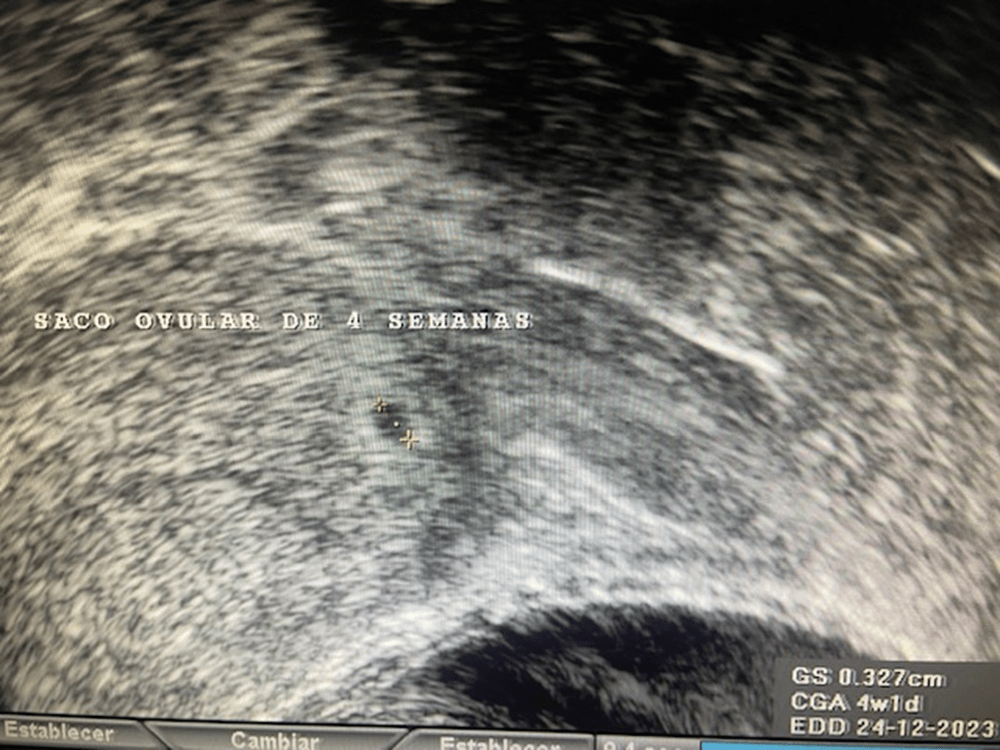

La primera imagen ecográfica de un embarazo la podemos obtener a las 4 semanas de gestación, cuando la embarazada solo lleva 2-3 días de atraso menstrual. Corresponde a una pequeña burbuja negra rodeada de un fino anillo blanco que se encuentra en la cavidad uterina. Suele medir unos 3 mm. Se le llama saco ovular.

Clínica ginecológica Dr. Francisco Valdivieso.